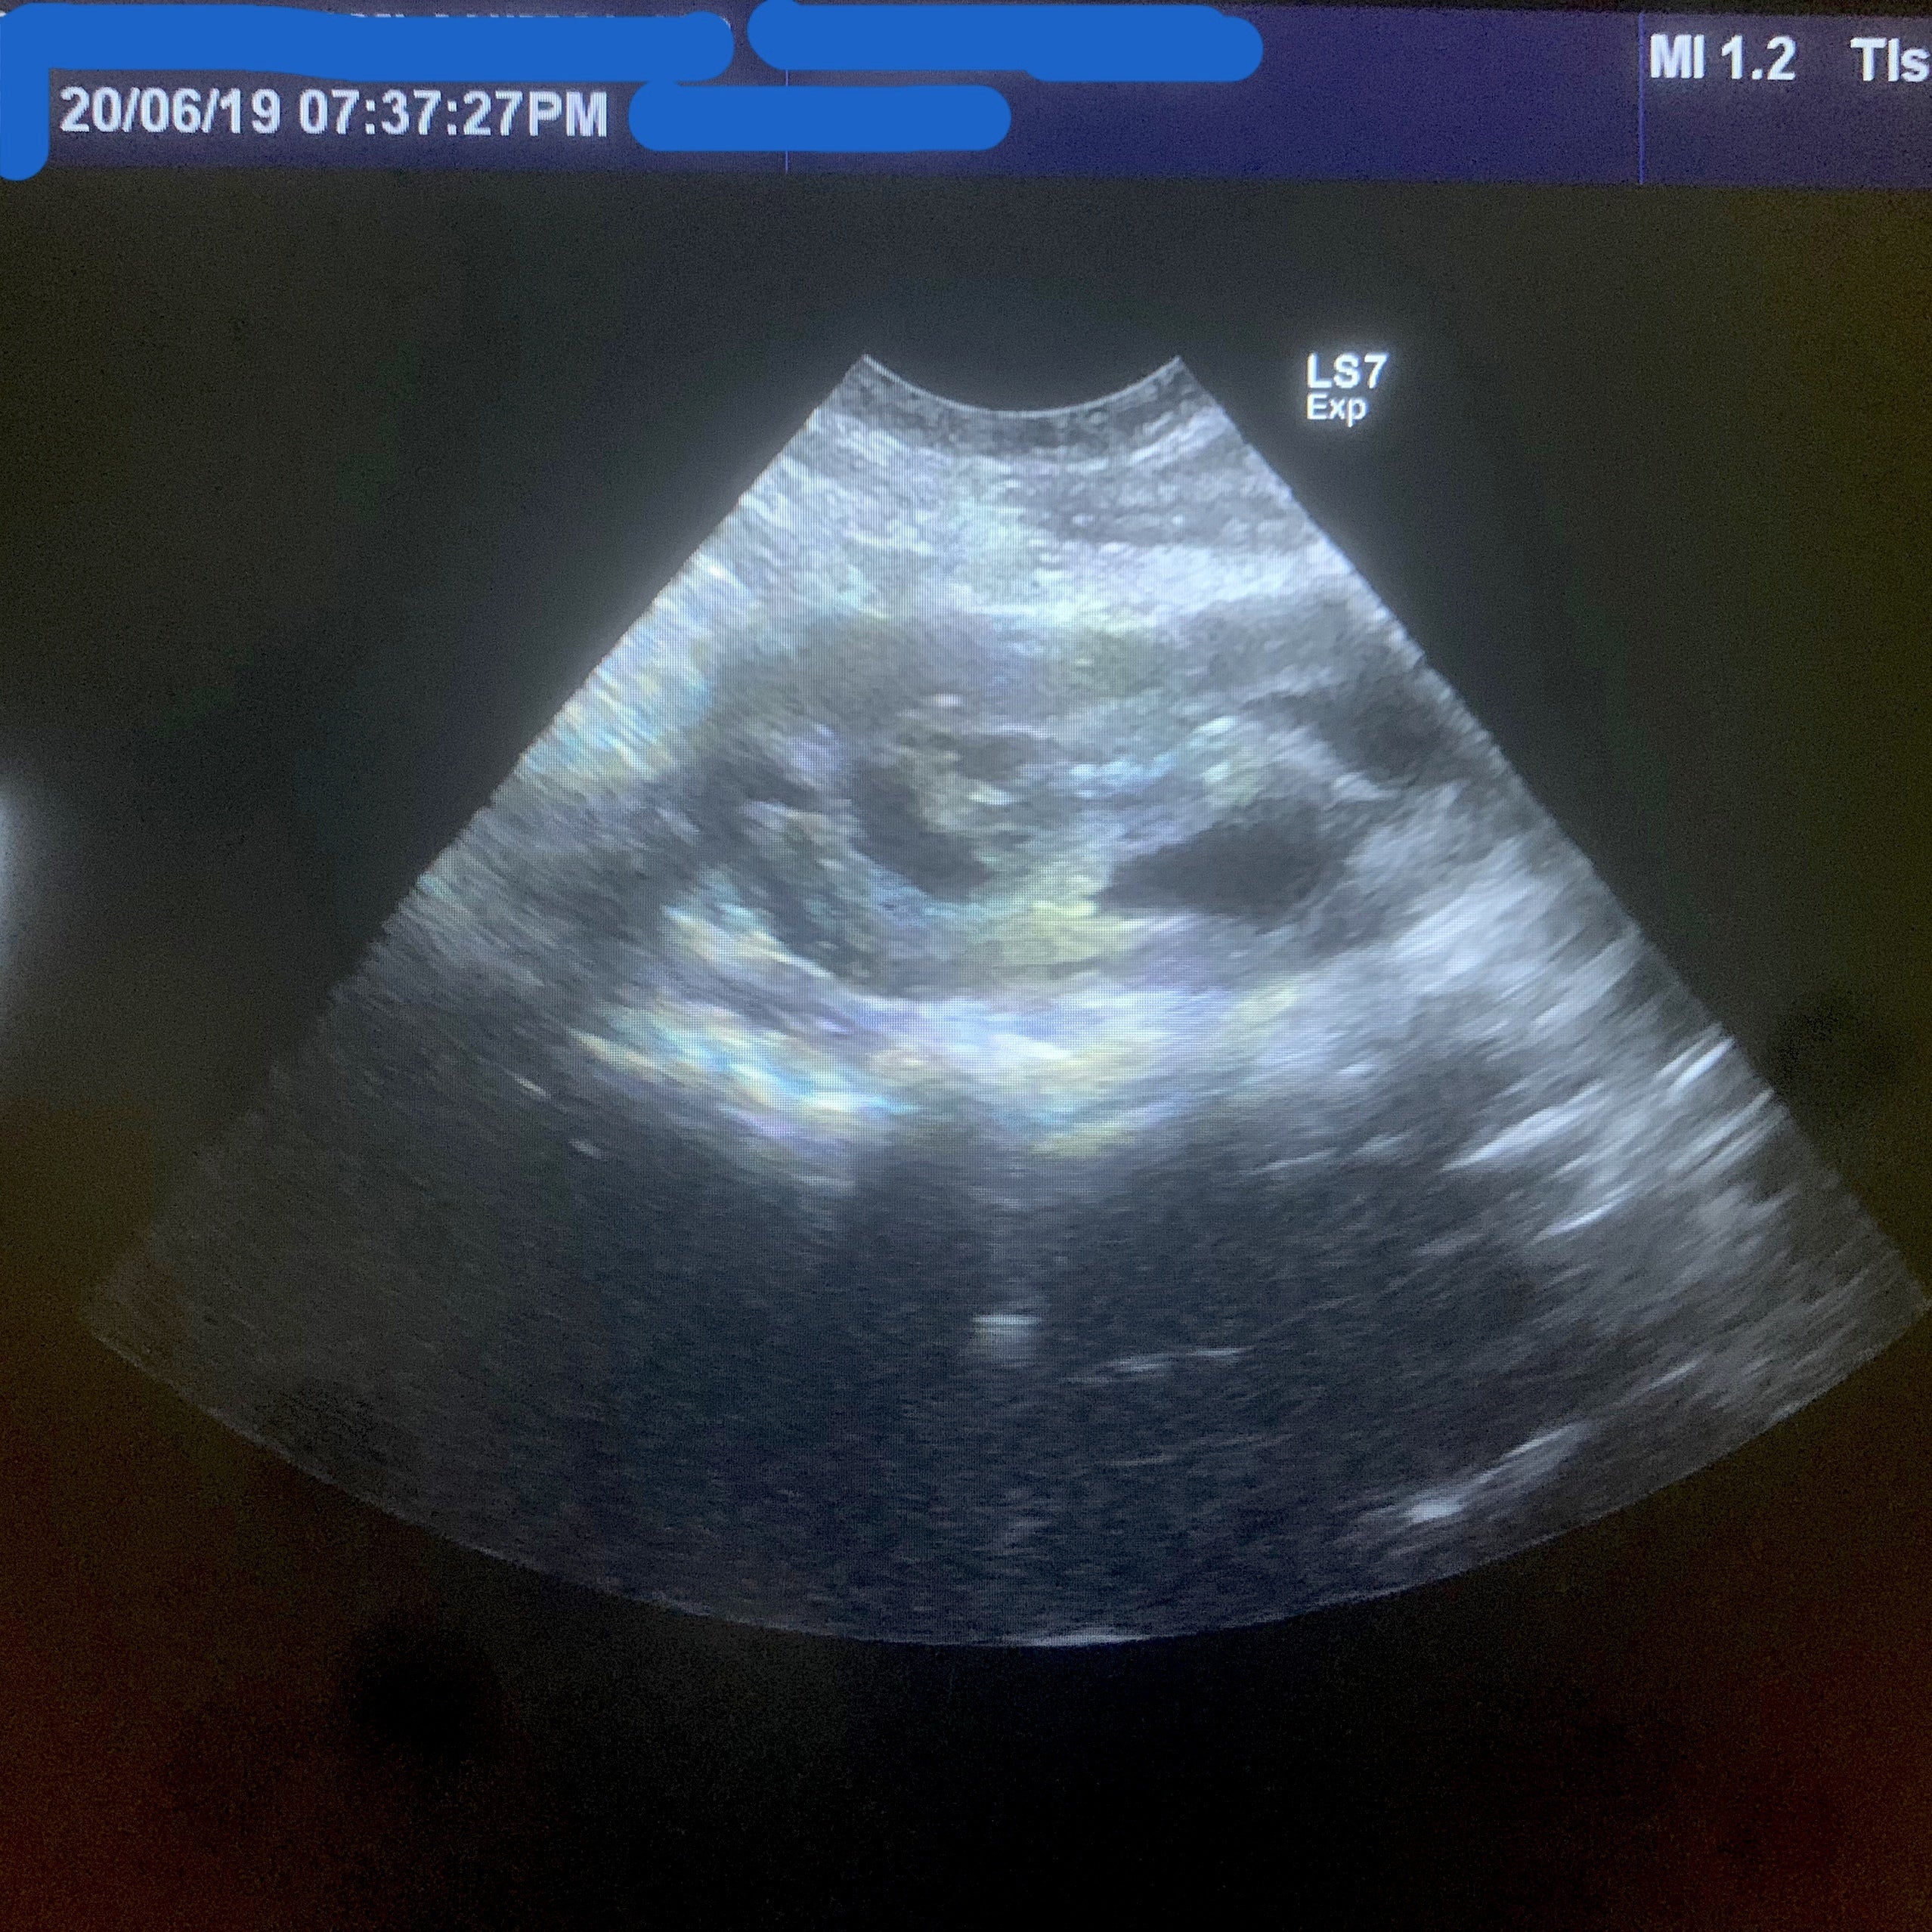

【6月19日】

鼻腔・尿路部洗浄。

17日に血尿のようなおしっこを

していたのでエコー検査を依頼。

診察結果を聞いてまた凹む。

今も膀胱の腫れがあり、

内膜が壊死を続けて蓄積している。

もしかしたら

投与している抗生物質が

内膜のターンオーバーを促進している

可能性がある。

尚且、耐性がつくと使える抗生物質が

なくなってしまうので一旦中断。

手術を行ったばかりで

まだ尿路も完成していないから

今カテーテルを入れることは不可。

もちろん、手術でとることも不可。

だけど、

前回尿路拡張したので

以前より解決法はある。

要約すると

今は経過観察しかない。